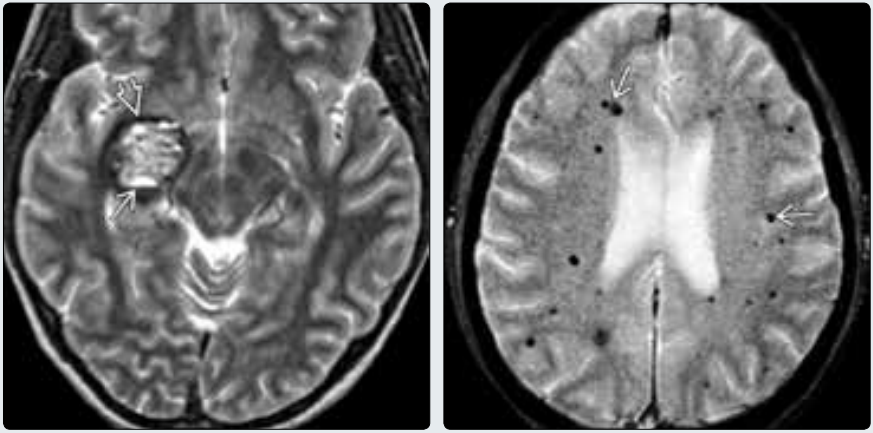

(左图)Zabramski 2型海绵状血管畸形,MR平扫横断位T2WI表现典型的“爆米花球”征。注意多个小房内的血-液平面→伴周围含铁血黄素环⇒。(右图)Zabramski 4型海绵状血管畸形,平扫MR横断位T2* GRE图像显示多发黑点,磁敏感加权序列表现为“晕征”→